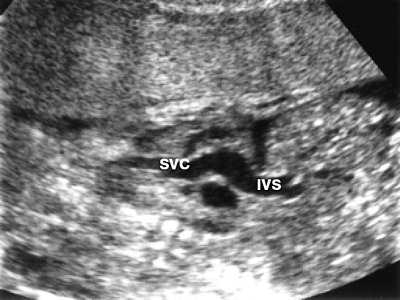

Второе наблюдение. Беременность 37 недель. У плода имеется выраженный выпот в перикарде и плевральной полости. Отмечено нарушение ритма пароксизмальная тахикардия. Анатомически сердце сформировано правильно. Эхокардиографически выявляется дилатация нижней и верхней полых вен (рис. 3) из-за нарушения венозного возврата крови.

Рис. 3. Дилатация нижней (IVC) и верхней (SVC) полых вен при антенатальном закрытии овального окна.

Межпредсердная перегородка значительно утолщена, наиболее это выражено в области овального окна (рис. 4), клапан которого закрыт (рис. 5). Поток крови через межпредсердную перегородку отсутствует.